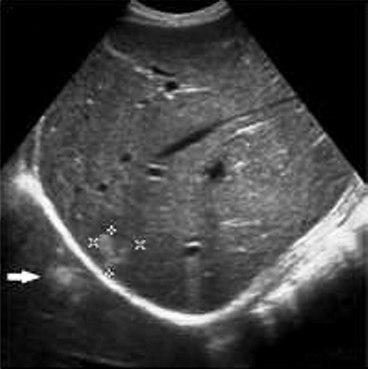

Thus when US beam encounters a strongly attenuating or highly reflective structure (structure with high attenuation), the amplitude of the beam distal to this structure is diminished (ultrasound beam is weakened), the echo returning from structures beyond (deeper) the highly attenuating structure will also be diminished, weakened (dark or hypoechoic band), resulting in poor resolution within the shadow.